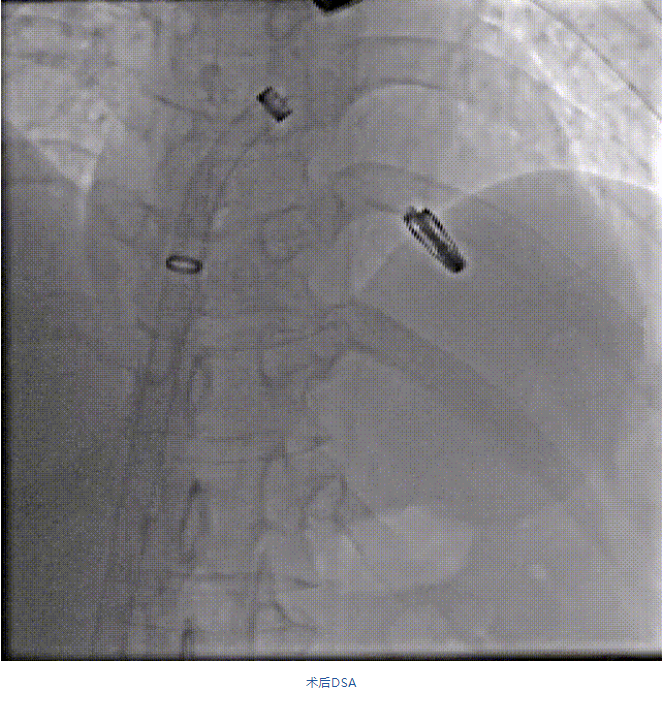

在阜外醫(yī)院潘湘斌教授團隊的支持下,手術(shù)經(jīng)股靜脈-房間隔入路,采用全身麻醉插管,在TEE和DSA引導(dǎo)下完成房間隔穿刺。置入JensClip瓣膜夾系統(tǒng)后,在左房調(diào)整瓣膜夾的位置和軸向,后進(jìn)入左室,在TEE引導(dǎo)下捕捉二尖瓣前后瓣葉,并關(guān)閉瓣膜夾。經(jīng)TEE反復(fù)確認(rèn)手術(shù)效果后最終鎖定并釋放瓣膜夾。術(shù)后即刻超聲顯示瓣膜夾位置穩(wěn)定,功能良好,二尖瓣反流由術(shù)前4+減少至微量,手術(shù)圓滿成功。